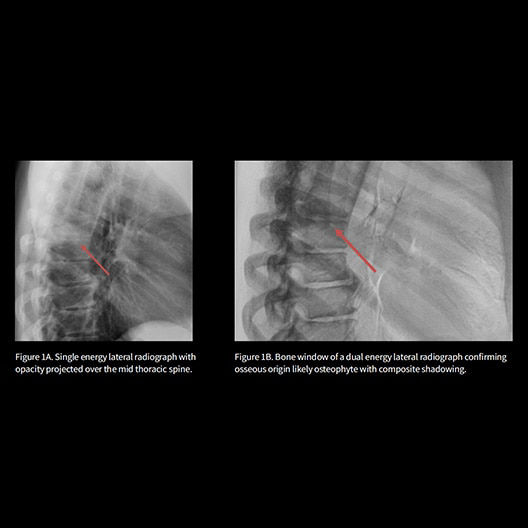

Dual Energy Subtraction

Helps eliminate obstructions from overlying bones while providing additional information.